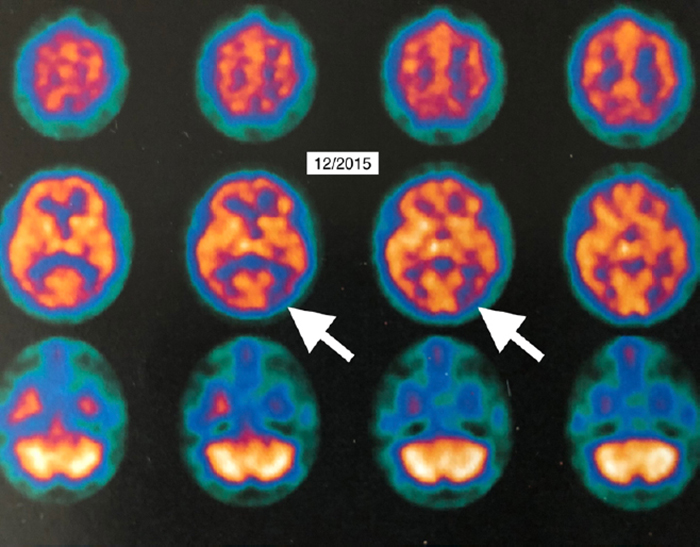

The patient underwent a total of 40 HBOT treatments – five days a week over 66 days. Each treatment consisted of 1.15 atmosphere absolute/50 minutes total treatment time. After 21 treatments, the patient reported increased energy and level of activity, better mood and ability to perform daily living activities as well as work crossword puzzles. After 40 treatments, she reported increased memory and concentration, sleep, conversation, appetite, ability to use the computer, more good days (5/7) than bad days, resolved anxiety, and decreased disorientation and frustration. Tremor, deep knee bend, tandem gain, and motor speed were also improved. Repeat 18FDG PET imaging one month post-HBOT showed global 6.5–38% improvement in brain metabolism.

The report also contains video imaging, including unique rotating PET 3D Surface Reconstructions, which allow the lay person to easily see the improvements in brain function.